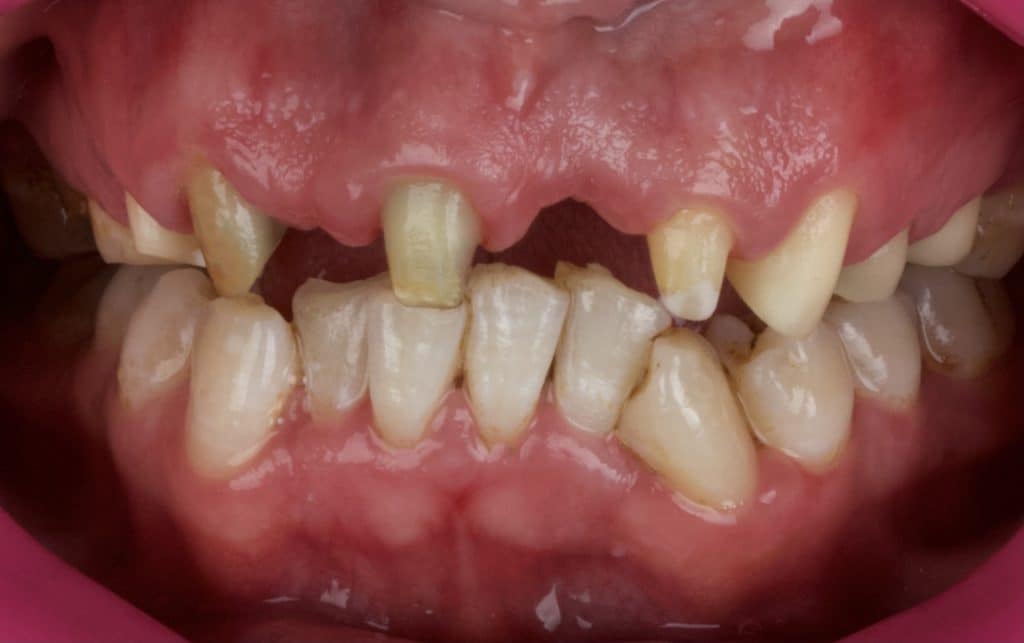

Initial situation